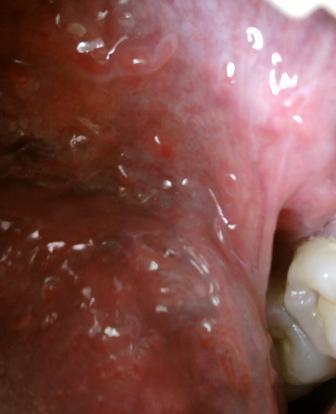

石家庄九州皮肤病医院 > 尖锐湿疣 > > > 男性尖锐湿疣初期治疗费用是多少对于尖锐湿疣性病的治疗费用,大家也是比较关心的话题,由于尖锐湿疣性病比较顽固,很多人认为尖锐湿疣的治疗费用会很高,专家在此表示:其实关于尖锐湿疣的治疗费用是受到多种因素的制约和影响的。初期是治疗疾病的最佳时期,不同的治疗方法,病情严重程度不同,都会影响治疗费用。

男性尖锐湿疣初期治疗费用是多少专家表示:关于尖锐湿疣的治疗费用包括两方面,一是检查费用,另外是具体的治疗费用。一般治疗尖锐湿疣不需要花费太高的费用,正规的专业医院在收费上严格遵守国家收费标准,一般的治疗费用在几百元左右。初期是治疗疾病的最佳时期,并且此时治愈的几率也是比较高的,治愈之后也是不容易复发的,这一点希望广大患者朋友们应该了解。

男性尖锐湿疣初期治疗费用是多少尖锐湿疣疾病传染性比较强,复发率也是比较高的,所以患病之后希望广大患者朋友们及时就诊,以减少疾病对人体带来的危害。现在治疗尖锐湿疣的方法是比较多的,但是只有选择适合自己病情的治疗方法,才能达到理想的治疗效果。以上就是石家庄九洲医院专家的解答,希望可以帮助到您。如有任何不清楚的可以拨打石家庄治疗尖锐湿疣的医院九洲皮肤病医院康复热线:0311-89109686和专家取得联系。我们的专家小组在医院诊治方面积累了丰富的临床经验,通过康复病人之间的口口相传,患者前来接受治疗的是最佳选择。